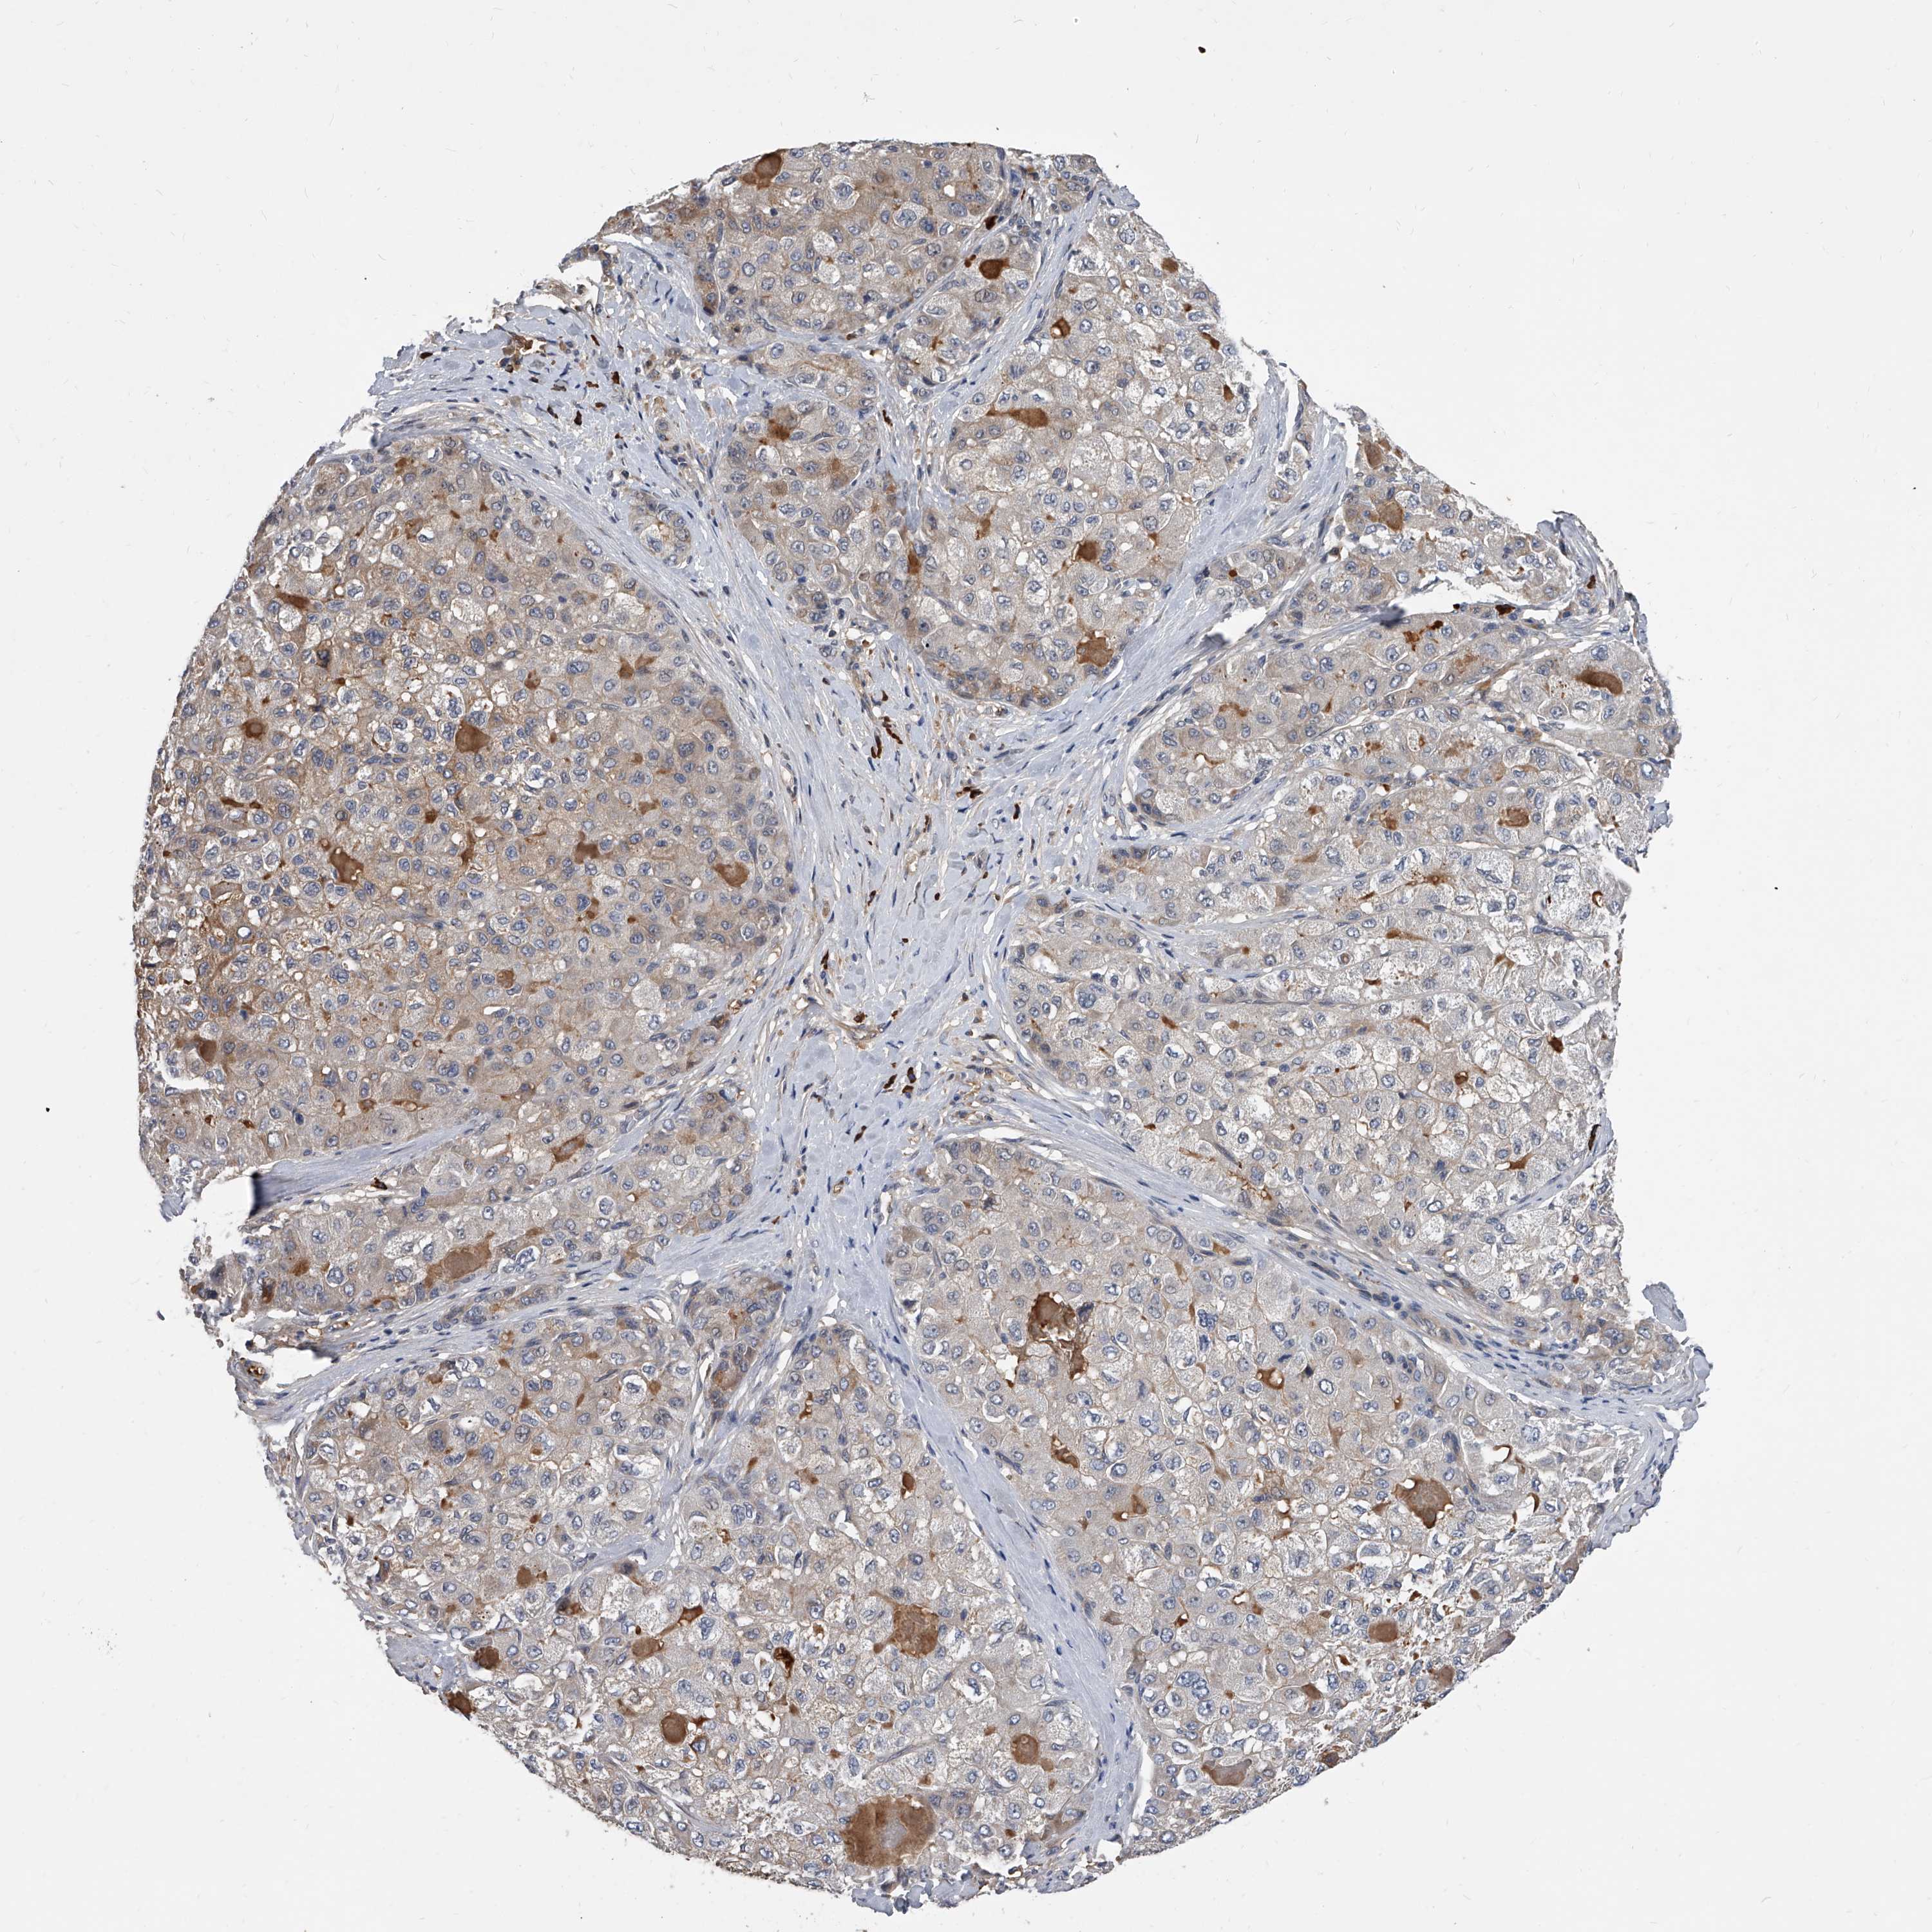

LIVER CANCER - Protein expressioni

A mouse-over function shows sample information and annotation data. Click on an image to view it in a full screen mode. Samples can be filtered based on level of antibody staining by selecting one or several of the following categories: high, medium, low and not detected. The assay and annotation is described here.

Note that samples used for immunohistochemistry by the Human Protein Atlas do not correspond to samples in the TCGA dataset.

Antibody stainingi

Antibody staining in the annotated cell types in the current human tissue is reported as not detected, low, medium, or high, based on conventional immunohistochemistry profiling in selected tissues. This score is based on the combination of the staining intensity and fraction of stained cells.

Each image is clickable and will lead to virtual microscopy that enables deeper exploration of all samples and also displays staining intensity scores, fraction scores and subcellular localization as well as patient and tissue information for each sample.

Antibody HPA030190

Staining

High

Medium

Low

Not detected

Intensity

Strong

Moderate

Weak

Negative

Quantity

>75%

75%-25%

<25%

None

Location

Nuclear

Cytoplasmic/membranous

Cytoplasmic/membranous,nuclear

Cholangiocarcinoma

Carcinoma, Hepatocellular, NOS